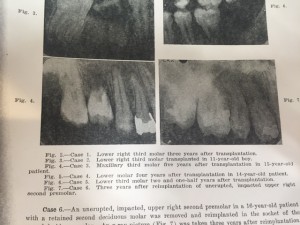

ケース1はFig2で、 『遠心根が吸収しました、抜歯の時に傷つけちゃったみたい。患者さんがWisconsinに引っ越して、今は連絡取ってない』だそうです

ケース2はFig3で、『11歳の少年に移植しましたが、歯根が出来ませんでした。このケースは歯冠が形成されてから移植しないとうまくいかない事をものがったてます』とのこと。見るも無残ですね。

ケース3はFig4で、移植後4年後のレントゲンだそうです。『P根は成長した。MB、BD根は成長が遅れを取っています』だそうです。いや、これはもうMB、BDは成長遅れてるんじゃなくて、成長しないんじゃない?笑

因みにEPTはポジティブとの事!!歯髄って不思議ですね。

ケース4はFig5で、『近心に年々ポケットができてきました』とのこと。原因は書いて無いです。